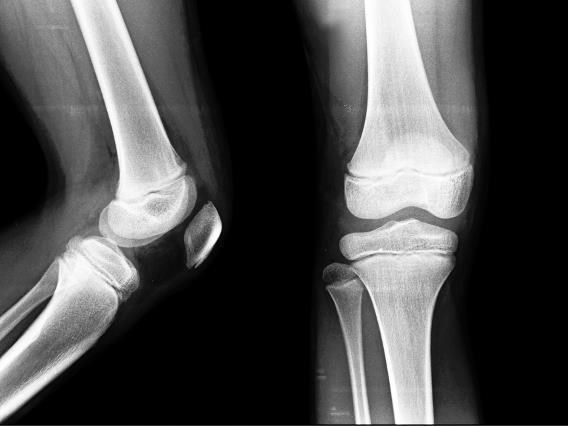

Соединительнотканный хрящ. Этот тип амортизирует кости позвоночника и встречается в коленном суставе. Соединительнотканный хрящ содержит много пучков коллагена, что делает его особенно прочным и сильным. Эластичный хрящ. Образует наружное ухо и надгортанник, который закрывает гортань при глотании. В эластичном хряще преобладает другой белок – эластин. Этот белок придает хрящу гибкость и объясняет, почему наши уши сначала согнутся, а только затем сломаются. ![]() Развитие костей Кости плода начинают развиваться в форме твердого хряща. Затем, в процессе роста организма, они сливаются и затвердевают. Этот процесс подчиняется основному закону структурной инженерии: исчезновение трубчатой структуры приводит к небольшому снижению прочности, но зато сопутствующее этому снижение веса становится крайне удобным для остальной части опорно-двигательной системы. Процесс замены хряща на кость (окостенение) начинается с тела кости и идет к ее концам, формируя там губчатую кость. Эпифизарный хрящ В детском возрасте мягкие диски гиалинового хряща, присутствующие в местах соединения эпифиза с диафизом (так называемый метафиз), проходят через стадию быстрого деления клеток. Хрящевая пластинка роста, или эпифизарная пластинка, – это участок, с которого кости начинают удлиняться. Новые клетки выталкивают старые к центру, из-за чего последние сплющиваются и затвердевают. По мере этого процесса кость постепенно удлиняется, а мы становимся выше. Паузы и старты К четырем годам наш мозг получает колоссальные объемы информации, для чего требуется огромное количество энергии. Однажды наступает момент, когда тело больше не может поддерживать одновременно рост и мозга, и самого организма. Поэтому принимает решение о временном замедлении роста костей, чтобы мозг мог потреблять всю необходимую энергию. ![]() На рентгеновском снимке эпифизарная пластинка выглядит как невидимая линия между двумя костями. У взрослых эпифизарная пластина затвердевает и отображается как белая линия. Во взрослом организме кости продолжают расти, но только в диаметре. В период полового созревания приоритеты меняются. К этому времени наш мозг уже дорос до того уровня, когда ему требуется меньше ресурсов. В качестве благодарности за это мозг высвобождает из гипофиза и гипоталамуса ряд половых гормонов, которые стимулируют последний скачок в развитии. Тогда эпифизарные пластинки начинают вновь создавать новые клетки с молниеносной скоростью. Это продолжается до тех пор, пока нам не исполнится двадцать лет. Затем пластинка роста перестает делиться, затвердевает и окостеневает. Мозговой отдел черепа Мозговой отдел черепа действительно уникален, ведь его образуют сразу восемь костей, или пластин. Изначально эти кости представляли собой отдельные структуры, которые после рождения стали срастаться. Наложение или смещение пластин выполняет сразу две функции: помогает головке малыша вытягиваться при прохождении через родовые пути и позволяет подстроиться под высокую скорость роста мозга. ![]() Роднички – это мягкие пространства между костями черепа новорожденных и младенцев. Со временем они полностью срастутся Она срастается с соседними костными клетками и образует эпифизарную линию. На рентгеновских снимках эпифизарная линия заметна в месте соединения диафиза и эпифиза. ![]() В период полового созревания мозг запускает последний скачок в развитии. Суставы и связки Суставы – это места соединения костей друг с другом. Связки – это эластичные пучки волокон соединительной ткани. Они выполняют поддерживающую функцию в суставах, брюшной полости и в тканях молочной железы. Типы суставов Суставы – это своего рода «место встречи», в котором кости могут состыковаться в комфортной среде и с минимальными трудностями. Все происходящее здесь зависит от типа сустава. ![]() Из всех шести синовиальных суставов наибольшую амплитуду движений обеспечивает шаровидный сустав (есть в плече и бедре). Синовиальные суставы. Это самые подвижные суставы. Они располагаются в костях коленей, локтей и кистей рук. Суставы выстланы гладким слоем соединительной ткани – синовиальной оболочкой, которая обеспечивает им большую амплитуду движений. Эта мембрана в одну клетку толщиной выделяет синовиальную жидкость, которая хорошо смазывает сустав и препятствует его высыханию. Синовиальные суставы заключены в прочную капсулу – суставную сумку, которая помогает суставу сохранять целостность и предотвращает нестандартные движения. По типу движения синовиальные суставы делятся на следующие группы: блоковидный, плоский, цилиндрический, шаровидный, седловидный и мыщелковый. Фиброзные суставы. В основном эти суставы зафиксированы и не двигаются. К этому типу относятся суставы черепа плода, более известные как швы черепа. Фиброзная ткань внутри суставов соединяет кости черепа друг с другом (см. «Мозговой отдел черепа» на стр. 91). В период активного мозгового роста суставы остаются гибкими. А затем, когда темп роста замедляется, швы начинают срастаться, становясь неподвижными. Хрящевые суставы. Хрящевая ткань соединяет две кости, придавая им частичную подвижность на малых расстояниях. Хрящевые суставы соединяют ребра с грудиной; именно поэтому грудная клетка способна расширяться. Но, как всегда, здесь не обошлось без исключений. К таким исключениям относятся межпозвоночные диски, которые, будучи фиброзными суставами, содержат хрящевую ткань (это фиброзно-хрящевые суставы, см. «Типы хрящей» на стр. 89), придающую им небольшую мобильность. Роль связок Связки – это пучки коллагеновых и эластиновых белковых волокон, их создают фибробласты. Сами фибробласты располагаются между волокнами и питаются губчатой тканью, которая переносится по кровеносным сосудам и нервам. Скелетно-мышечные связки проходят через надкостницу и соединяют две кости, образуя сустав. Кроме того, связки препятствуют вывихам костей, ограничивая их движение. Внутренние органы не плавают в животе; их удерживают на месте различные структуры, в том числе и брюшные связки. Также связки поддерживают форму и тонус женской груди. |